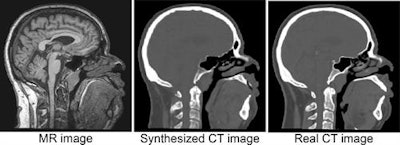

An example of a CT image derived from MRI using deep learning, with the real CT image aligned for reference (based on https://link.springer.com/chapter/10.1007/978-3-319-68127-6_2). The synthesized CT images closely match real reference CT images, potentially leading to a reduction in treatment planning time, patient discomfort, and CT radiation dose. This work was performed in collaboration with the radiotherapy department. All images courtesy of Jelmer Wolterink, PhD, and colleagues.Išgum, an associate professor and group leader of the Quantitative Medical Image Analysis (QIA) unit in the Image Sciences Institute, highlighted the following deep-learning topics for future investigation:

- Image-to-image synthesis. Images can be translated from one domain to another, e.g., synthesis of pseudo-CT images from brain MR and synthesis of routine-dose CT images from low-dose CT. Acquisition of certain images may be omitted to save time and reduce costs, patient discomfort, and CT radiation dose. The network can predict a Hounsfield unit value for each voxel in the MR image, and noise can be removed.